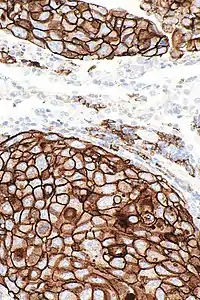

Not all patients respond to PD-1/PD-L1 inhibitors. The FDA has approved several assays to measure the level of PD-L1 expressed by tumor cells, in order to predict the likelihood of response to an inhibitor. PD-L1 levels have been found to be highly predictive of response. Higher mutation burden is also predictive of response to anti-PD-1/PD-L1 agents.[8]